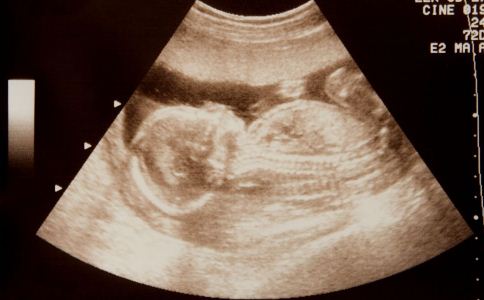

2、孕22—28周:超聲心動圖

有研究發現,胎兒在孕3周的時候,心髒畸形就已經確定了。過去產科的超聲檢查只能看看胎位,胎心跳動,面部、頭部和肢體的情況,現在醫學技術發展了,通過超聲心動圖能夠發現更小更細微的結構變化,尤其是心髒結構,診斷率可以達到98%。因此,孕婦在懷孕22—28周時就要檢查孩子的心髒情況。對有先心病的胎兒,做到盡早診斷。能夠矯正的孩子,定期監測胎兒心髒功能,待分娩後轉診至小兒心髒專科進行手術治療。對於查出的嚴重、無法徹底矯治的先心病患病胎兒,建議及時終止妊娠。